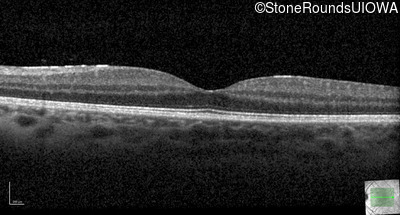

Optical Coherence Tomography - Right - 20/25 -2

Exemplar / OCT Stack